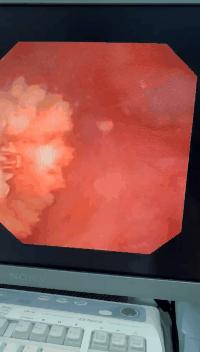

(肾结石碎石 前后对比)